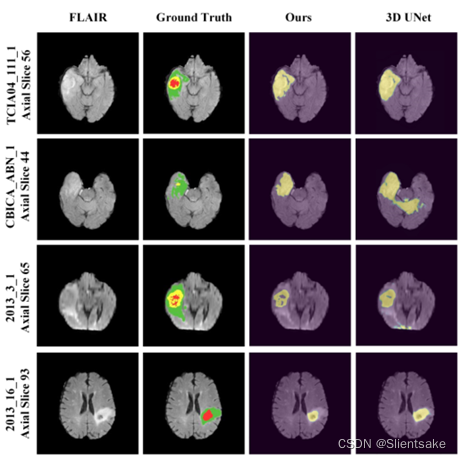

为了进一步评估分割输出,作者将所提出方法的分割输出与地面真实值进行比较。图7显示,所提出的CANet可以有效地预测正确的区域,包括小肿瘤核心和复杂边缘,而其他现有技术方法无法做到这一点。

与其他方法相比,提出的方法使用较少的时间收敛到较低的训练损失。利用强大的特征交互图和提出的融合模块CGA-CRF,CANet实现了令人满意的脑胶质瘤轮廓。随着训练时间的增加,CANet对分割图进行微调,并成功地检测出小肿瘤的核心和边界。作者在图9中展示了提出的CANet和3D UNet的概率图。从图9可以看出, CANet可以定位目标肿瘤的形状轮廓以实现精确分割,而标准3D UNet可能导致不确定性,例如图9中的第一行(WT概率图)和最后一行(TC概率图)。此外,标准U-Net可能将健康环境误分类为肿瘤组织,例如图9中的第二行(WT概率图)和第三行(ET概率图)。

图9:提出的CANet和3D UNet的分割概率图示例。从上到下的列表示不同的患者病例。从左到右的行分别表示FLAIR数据、地面真相标注、CANet在CG-ACRF中经过5次迭代生成的注意图和3D UNet生成的注意图。